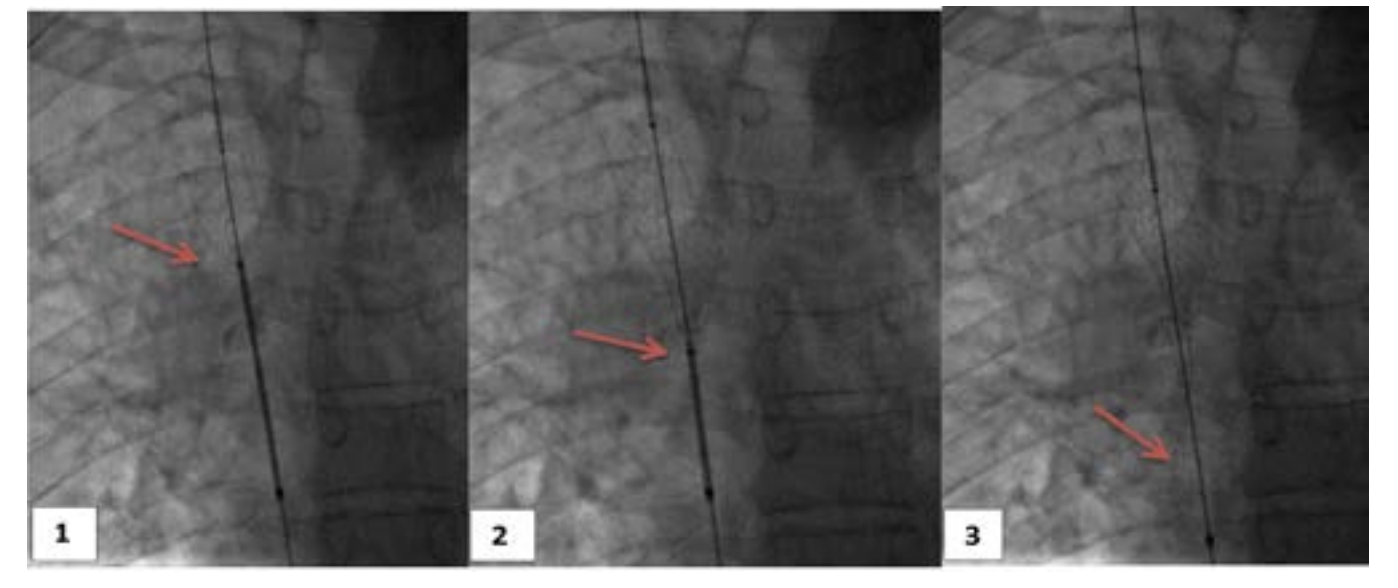

The venacavogram confirmed the absence of thrombus and revealed a stenosis in 3 cases and an occlusion in 2 cases. The stenosis/occlusion localization was the SVC in 3 cases and both SVC and the innominate venous trunk (IVT) in 2 cases.

From a therapeutic point of view, endovascular treatment of SVCS had been performed under local anesthesia. Percutaneous vena femoral approach was carried out in 2 cases. Three patients also required the use of the basilica pathway. Before stenting, the caval stenosis was dilated two or three times for almost 10 minutes by means of balloon inflation to the estimated diameter in three cases. We also routinely performed post-stent dilatation. In all procedures, a self-expanding stent had been deployed. The details regarding the stent deployed are summarized in Table 1. As an immediate follow-up, the patients experienced a quick relief of symptoms between 48-72 hours.